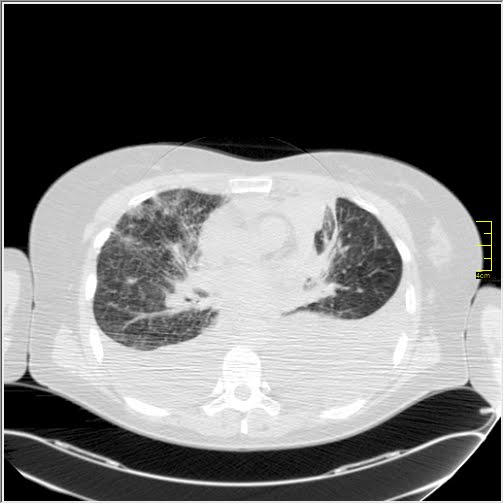

2. CT nalaz je bio više mešavina nalaza kod H1N1, SARS-1 i MERS. Ground glass koje su se javljale su bile grube strukture, uglavnom bez crazy paving i sa težnjom da se brzo šire ka sredini i izazovu citokinu oluju. Trakcione bronhiektazije nisu dominirale ali je bilo znaka trakcije. Nije bilo puno vaskularnih zadebljanja

1. Dominiraju brojne ground glass koje su bile fine strukture, kada se posmatraju liče na paukovu mrežu. One grube strukture iz prvog talasa se retko viđaju. Retke su i crazy paving ali je značajno više tromboembolija, srčanih udara i krvarenja u mozgu.

2. Prisutne su vrlo fine strukture ground glass, u II fazi su obavezne crazy paving, prisutne su trakcione bronhiektazije, subpleuralne fibrozne trake. Sve kao po švajcarskom satu. Naravno, stanje nije isto kod različitih pacijenata ali je prilično pravilno